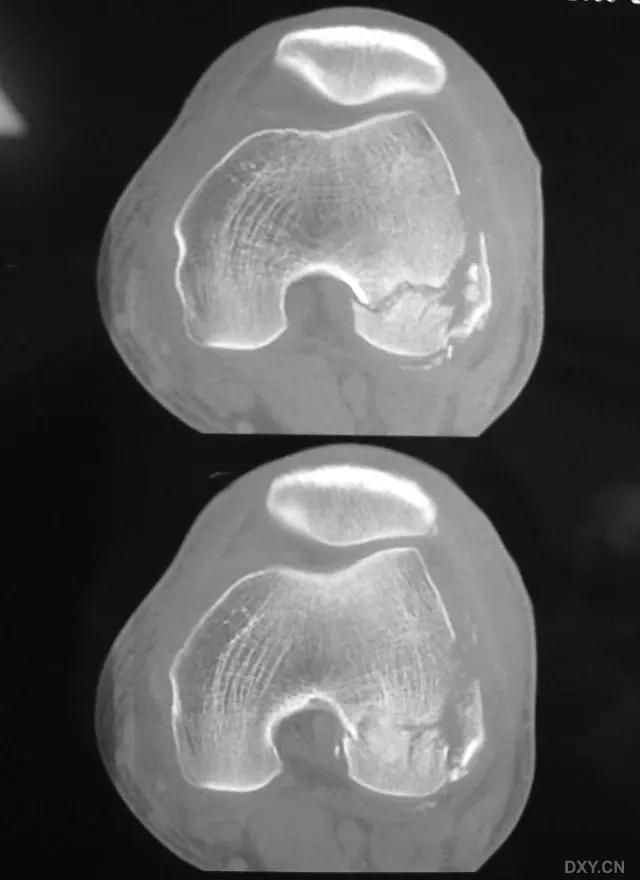

11. Bumper 骨折 (保险杆骨折)

是汽车保险杠撞击膝关节外侧,导致的胫骨平台粉碎性骨折,伴有软骨面挫裂和腓骨头骨折。初诊,X 线上正侧位很容易忽略平台的粉碎性,CT 平扫及重建可明确伤情,MRI 可了解副韧带及叉韧带情况。